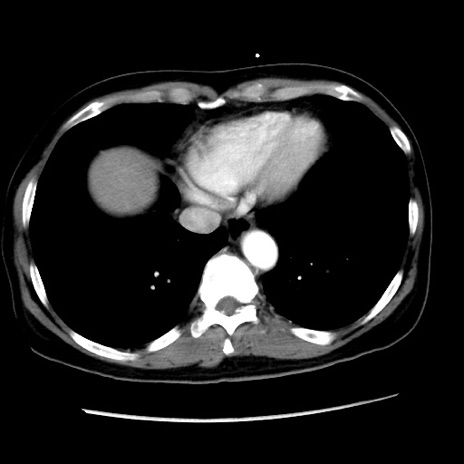

症例10(横断像)

【症例】 50歳代女性

【主訴】 腹痛

【現病歴】前日生レバーを食べた。今朝に排便あり。 昼前に突然発症の腹痛を生じ、当院救急外来を受診した。

【身体所見】 意識清明、腹部:平坦、軟、下腹部やや左を中心に圧痛・反跳痛あり、筋性防御あり